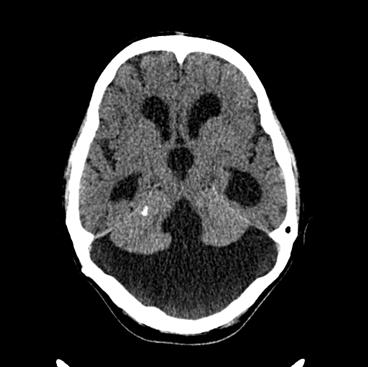

On CT images acute bleeding always presents as hyperdensity. (One has to keep it mind that hyperdensity of the blood is affected by the hematocrit levels, hence making the diagnosis more difficult.) Intraparenchymal blood is dominated by a destructive appearance (mass-effect) and it is surrounded by hypodensity as a sign of perifocal edema. It often breaks into the ventricles. In patients lying in a supine position they collect (sediment) at the occipital horn of the lateral ventricles, creating a hyperdense liquid-to-liquid levels. Later on, the density of blood decreases and shows a peripheral ring or rim-like contrast enhancement without mass-effect.